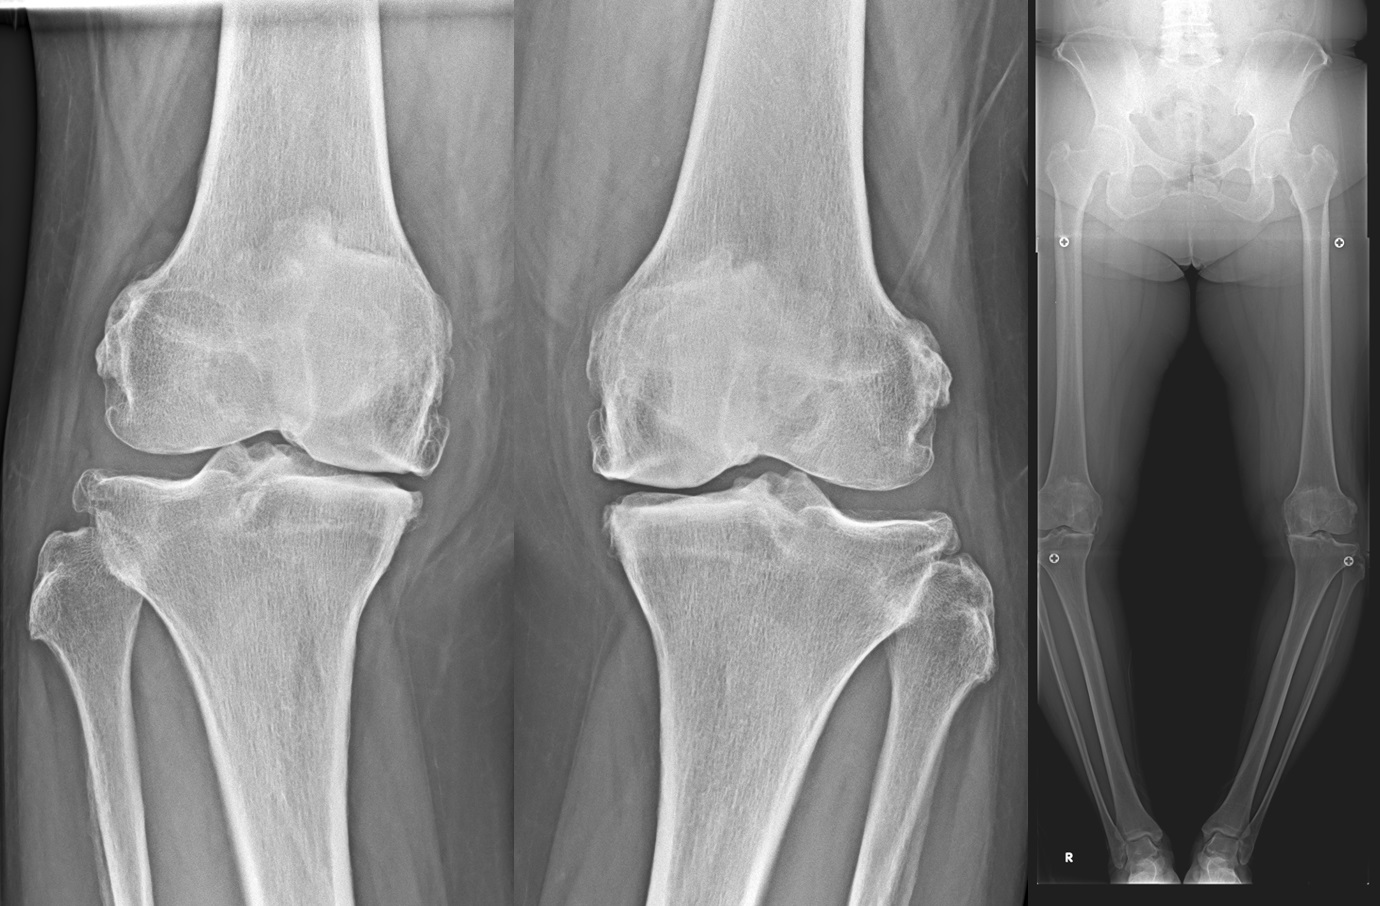

人工膝関節単顆置換術(unicompartmental knee arthroplasty: UKA)

膝関節の内側または外側のみの変形に対して適応があります。

片側のみの人工関節置換術であることから、体への負担が少なく、早期より痛みが改善し歩行が可能となります。